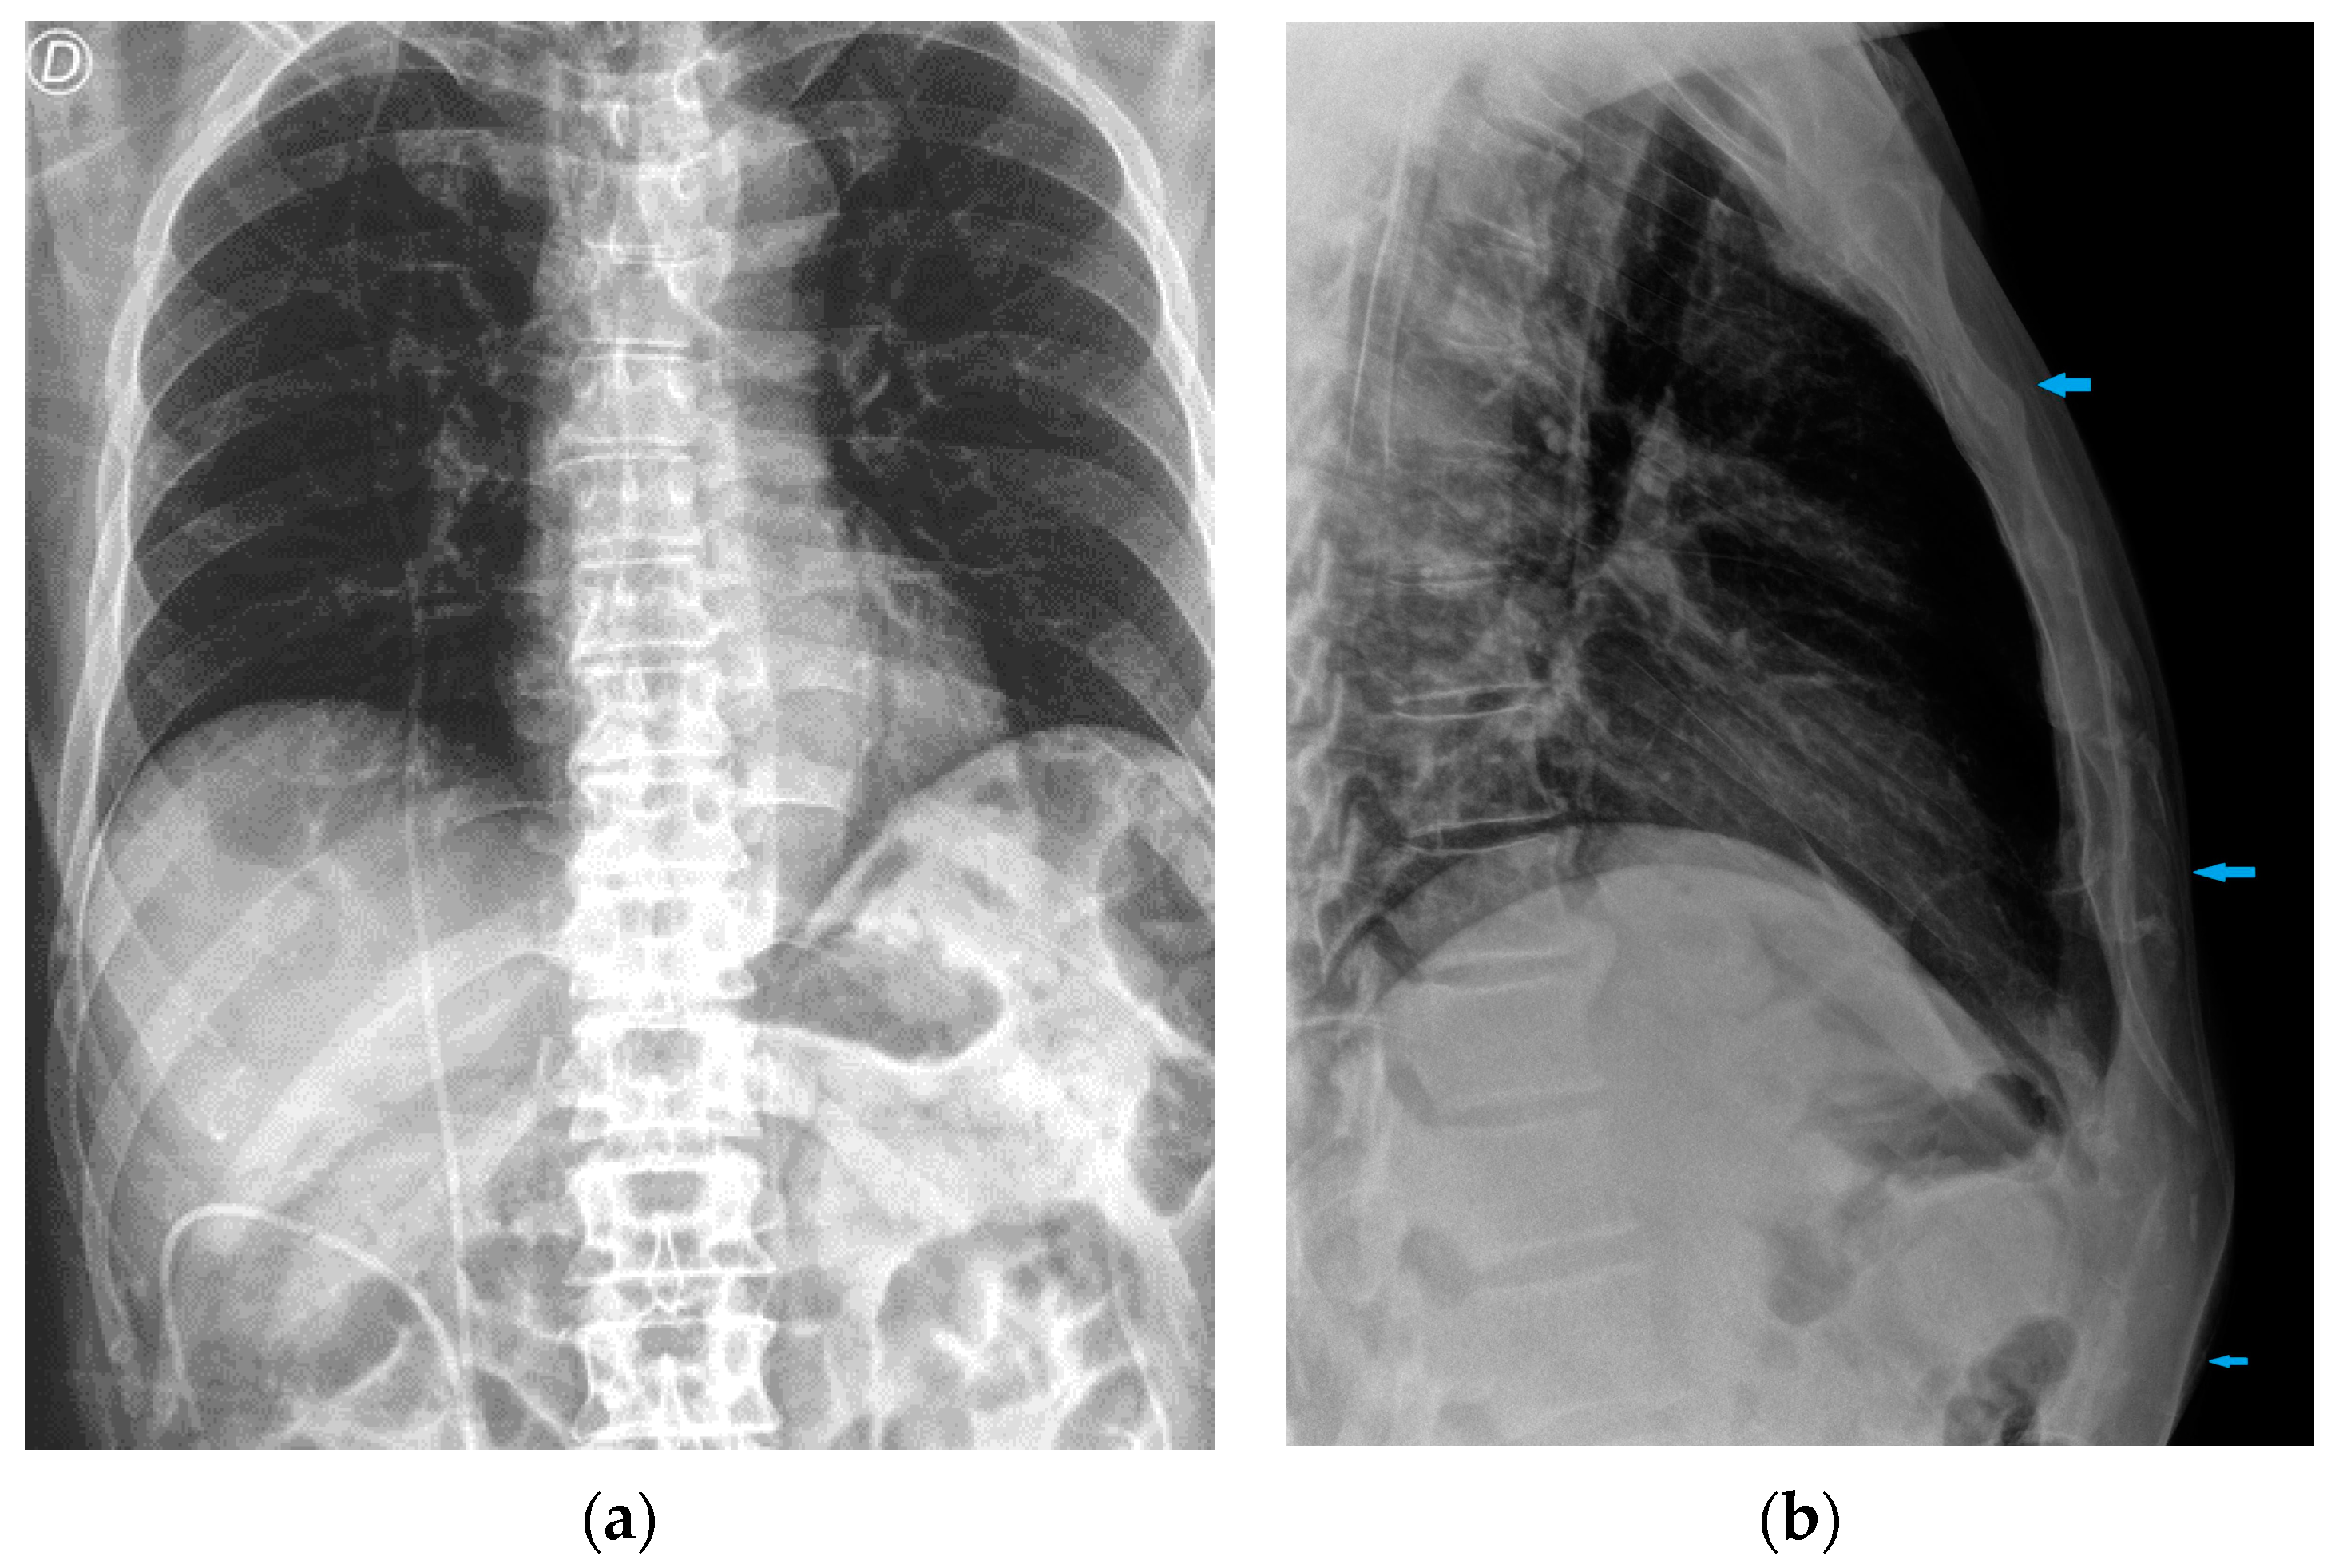

Figure 28.

Right apical chest drainage tube in patient with right pneumothorax (blue arrow) on PA (a) and LL (b) projections.

Figure 29.

Post-operative CXR illustrating two chest tubes with their tip in the right apical region. Note that whereas in the PA projection (a), the tubes seem to follow the same course, the LL view (b) clearly differentiates between an anterior and a posterior course.